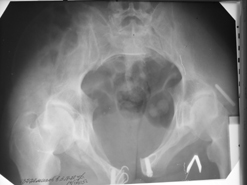

Диагноз : Сочетанная травма. ЗЧМТ. Перелом свода черепа. Ушиб головного мозга.Разрыв лонного и крестцово-подвздошного сочленений с нарушением целостности тазового кольца, с массивной забрюшинной гематомой и пропотеванием в брюшную полость. Перелом 10 ребра справа, осложненный гемопневмотораксом справа, правосторонней пневмонией на фоне ушиба правого легкого. Шок 3-4 ст. Больной поступил в отделение 07.03.2005г. в 16.00 в экстренном порядке через 30 минут после автодорожной травмы.Доставлен КСП. При поступлении состояние больного крайне тяжелое, явления травматического шока, А/Д-80/60 мм.рт. ст. ЧСС-120.В экстренном порядке поднят в операционную, интубирован, совместно с диагностическими мероприятиями лечение шока.При осмотре выявлены перелом 10 ребра справа, разрыв лонного и правого крестцово-подвздошного сочленений. Имеется линейный перелом теменной и височной костей слева с переходом на основание. Диагностическая лапароскопия 07.03.2005г. в 16.30-массивная забрюшинная гематома малого таза.Оставлена контрольная, дренажная трубка.Учитывая кровь в моче произведена цистография - данных за разрыв мочевого пузыря не найдено. Больной переведен в реанимационное отделение.За 08.03.2005г. из брюшной полости выделилось до 1500,0 мл, крови, часть крови реинфузирована. 08.03. в 06.30 наложен торокоцентез справа,удалено 100,0 мл. крови и 200,0 мл. воздуха .. Учитывая продолжающеееся кровотечение в брюшную полость из перелома костей таза, для исключения возможного разрыва внутренних органов 09.03.2005г. произведена Видеолапароскопия., на которой повреждения органов брюшной полости не выявлено.Одновременно произведен шов лонного сочленения проволокой и винтами, с одномоментным наложением стержневого аппарата на кости таза, с целью уменьшения кровотечения из разрывов тазовых сочленений, дренирование гематом. В последующем состояние больного оставалось тяжелым. 10.03.наложена нижняя трахеостома.Далее неоднократно производилась лечебно-диагностическая ФБС.С 10.03 выявлена правосторонняя плевропневмония. КТ головного мозга от 10.03-субарахноидальноекровоизлияние.Срединные структуры не смещены. КТ-контроль от 15.03-открытая моновентрикулярная гидроцефалия4 желудочка. Полисинусит. Постепенно состояние больного медленно прогрессировало к улучшению.С 24.03 переведен на самостоятельное дыхание, а 09.03 переведен в травматологическое отделение.Аппарат стержневой снят из-за перелома стержня (раскрутил больной самостоятельно).После госпитализации в наше отделение проведено дополнительное обследование Рентгекнография, КТ.Хотелось бы услышать Ваше мнение о дальнейшей тактике.-- С уважением, Leonid

Углядел билатеральное повреждение таза. Имеется вертикальная нестабильность со стороны перелома боковой массы крестца, ротационная с контрлатеральной стороны - чрезподвздошный разрыв кп сочленения. Разрыв лона, запирательные отверстия вроде целы.

DS. на сегодняшний день: Вертикальная двусторонняя нестабильная деформация таза, неправильно срастающийся перелом боковой массы крестца слева, срастающийся перелом крыла правой подвздошной кости, застарелый частичный разрыв правого кп сочленения, застарелый разрыв лонного сочленения.

План жизни - оперативное лечение. ЧКО таза (кольцевая опора), последовательная фиксация задних отделов с низведением перелома крестца, синтез лона пластинами, илиосакральное блокирование.